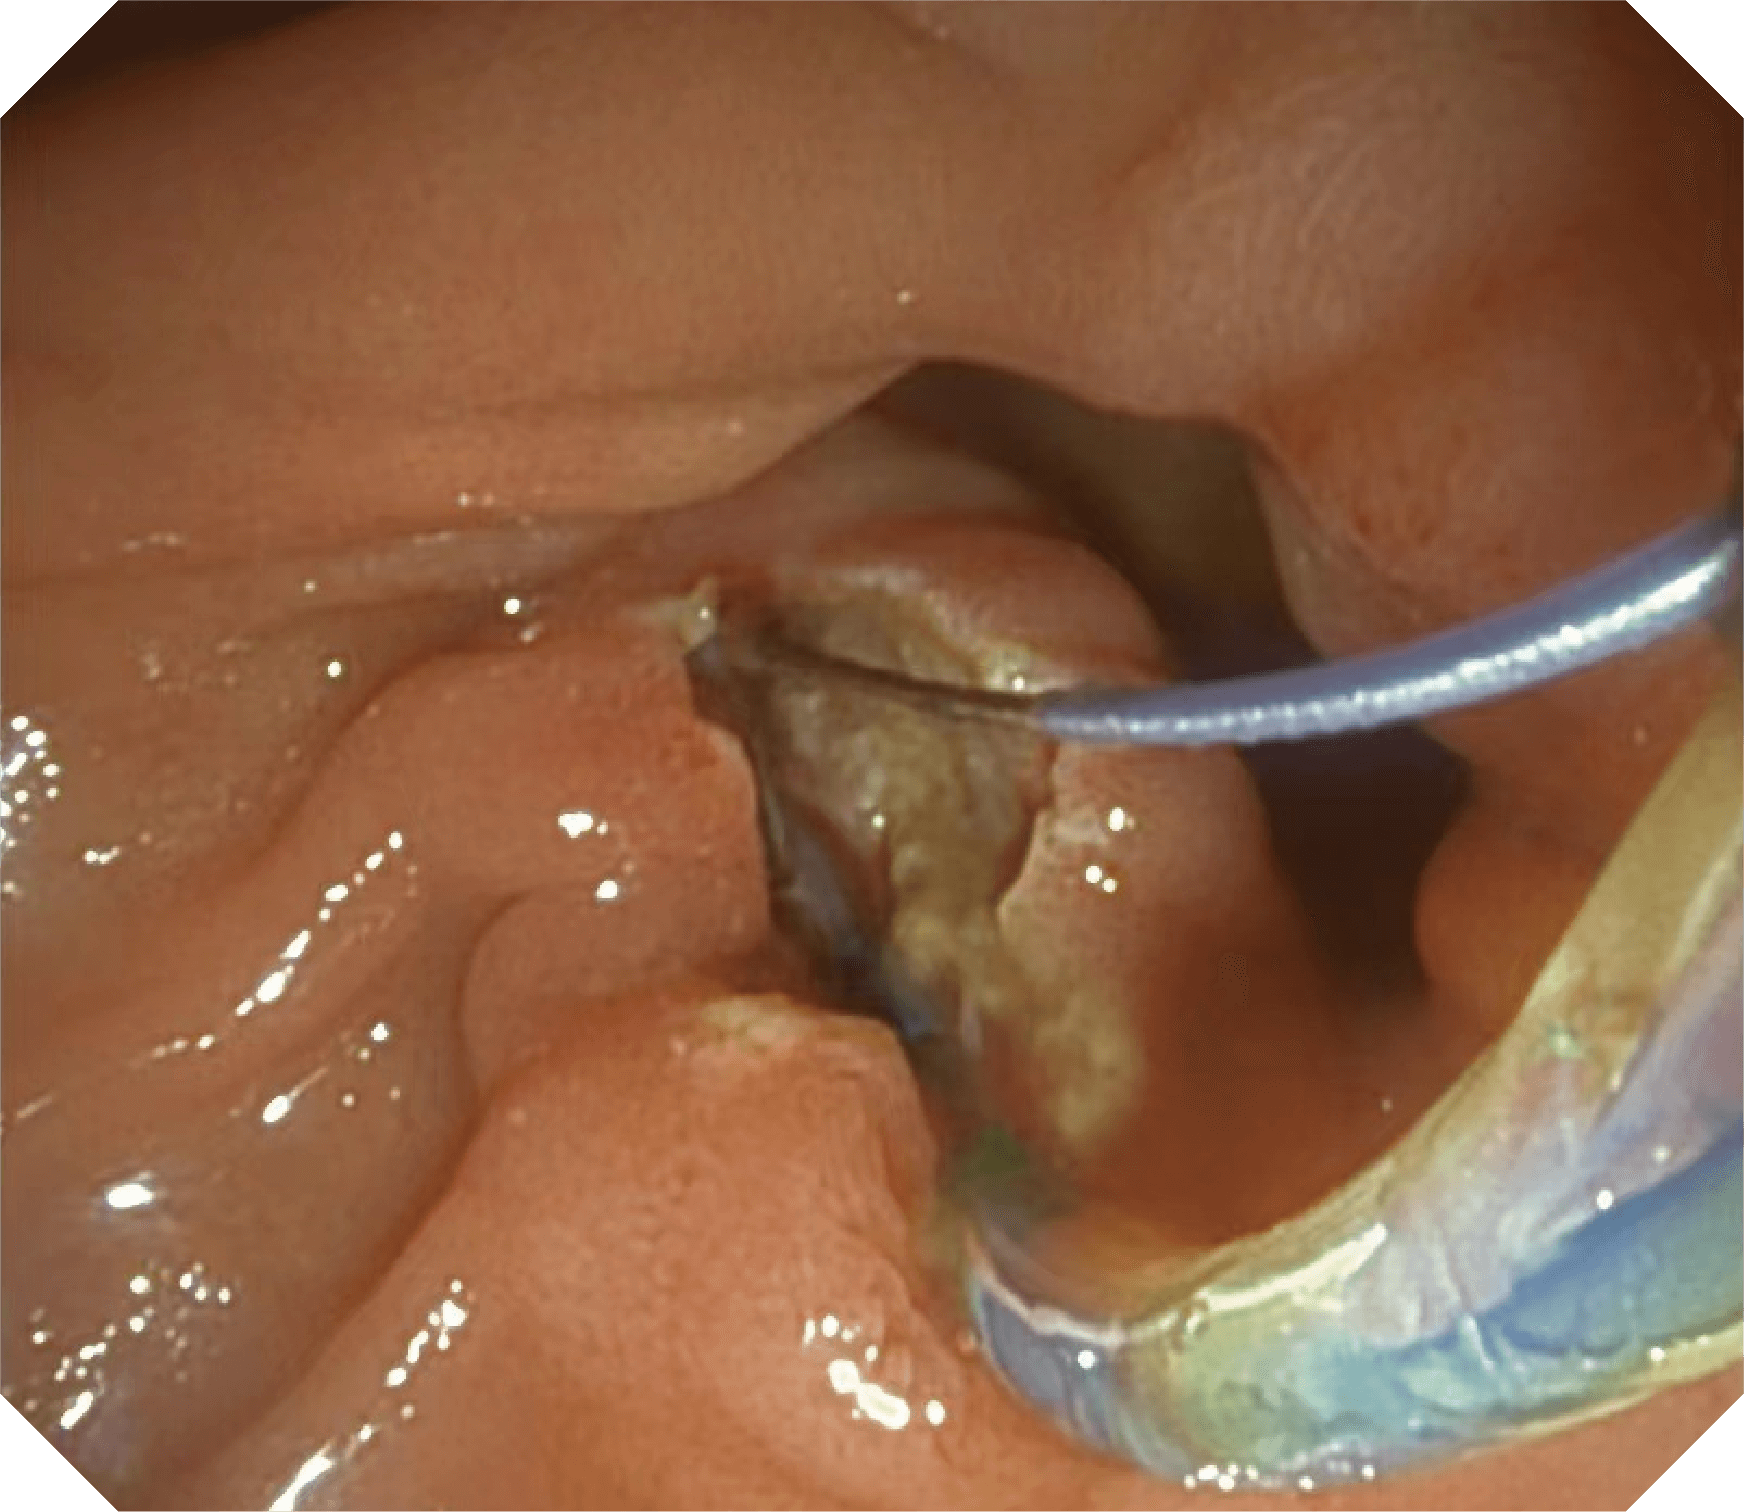

4.2mm大钳道,器械交换更顺畅

更好的通过性,更稳定的镜体支撑力